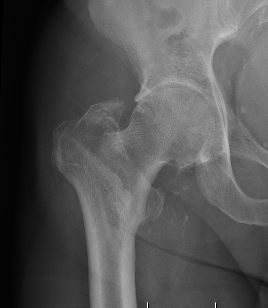

Type II Reverse Oblique Type

Inherently unstable - tendency of femoral shaft fragment to shift medially

Reverse oblique fractures

Stability

Depends on medial cortical reduction

Unstable (AO 31.A2 + 31.A3)

- intact lateral wall

- posteromedial cortical fracture

- reverse oblique

- subtrochanteric extension